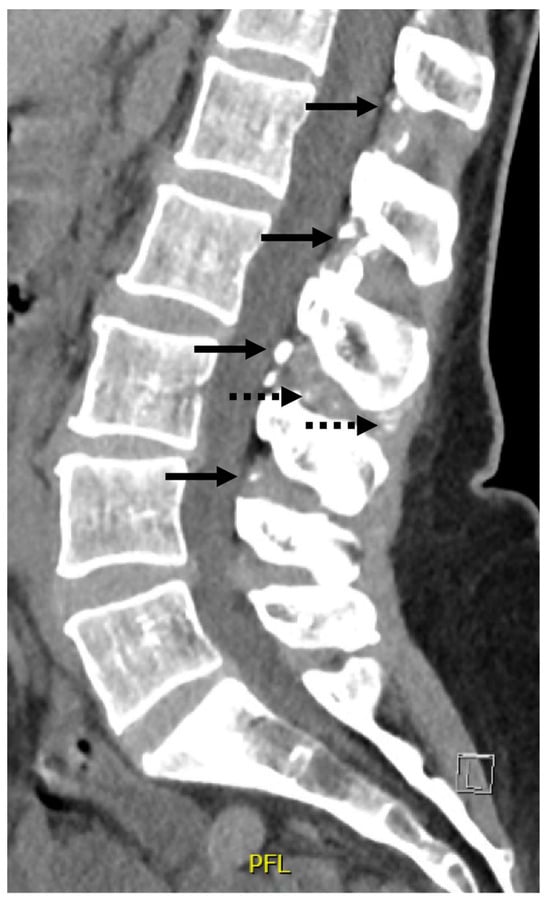

Several medical imaging examinations had already been carried out in previous years. A whole-body bone scan, performed three years earlier, showed no argument in favor of an inflammatory arthropathy but did show signs of degenerative joint disease mainly affecting the shoulders and hands. Three months before the consultation, as lower back pain was getting worse, a lumbar CT scan was performed, which demonstrated diffuse degenerative disc disease with atypical heterotopic calcifications of the yellow ligament and interspinous ligaments, suggesting abnormal extra-articular calcium accumulation and calcium pyrophosphate deposition disease (Figure 1). Raynaud’s phenomenon had been evaluated several years ago by video-capillaroscopy, the results of which were normal.

Figure 1.

Lumbar CT scan. The lumbar CT scan, performed three months before the consultation, demonstrated diffuse degenerative disc disease with atypical heterotopic calcifications of the yellow ligament (arrows) and interspinous ligaments (dotted arrows).